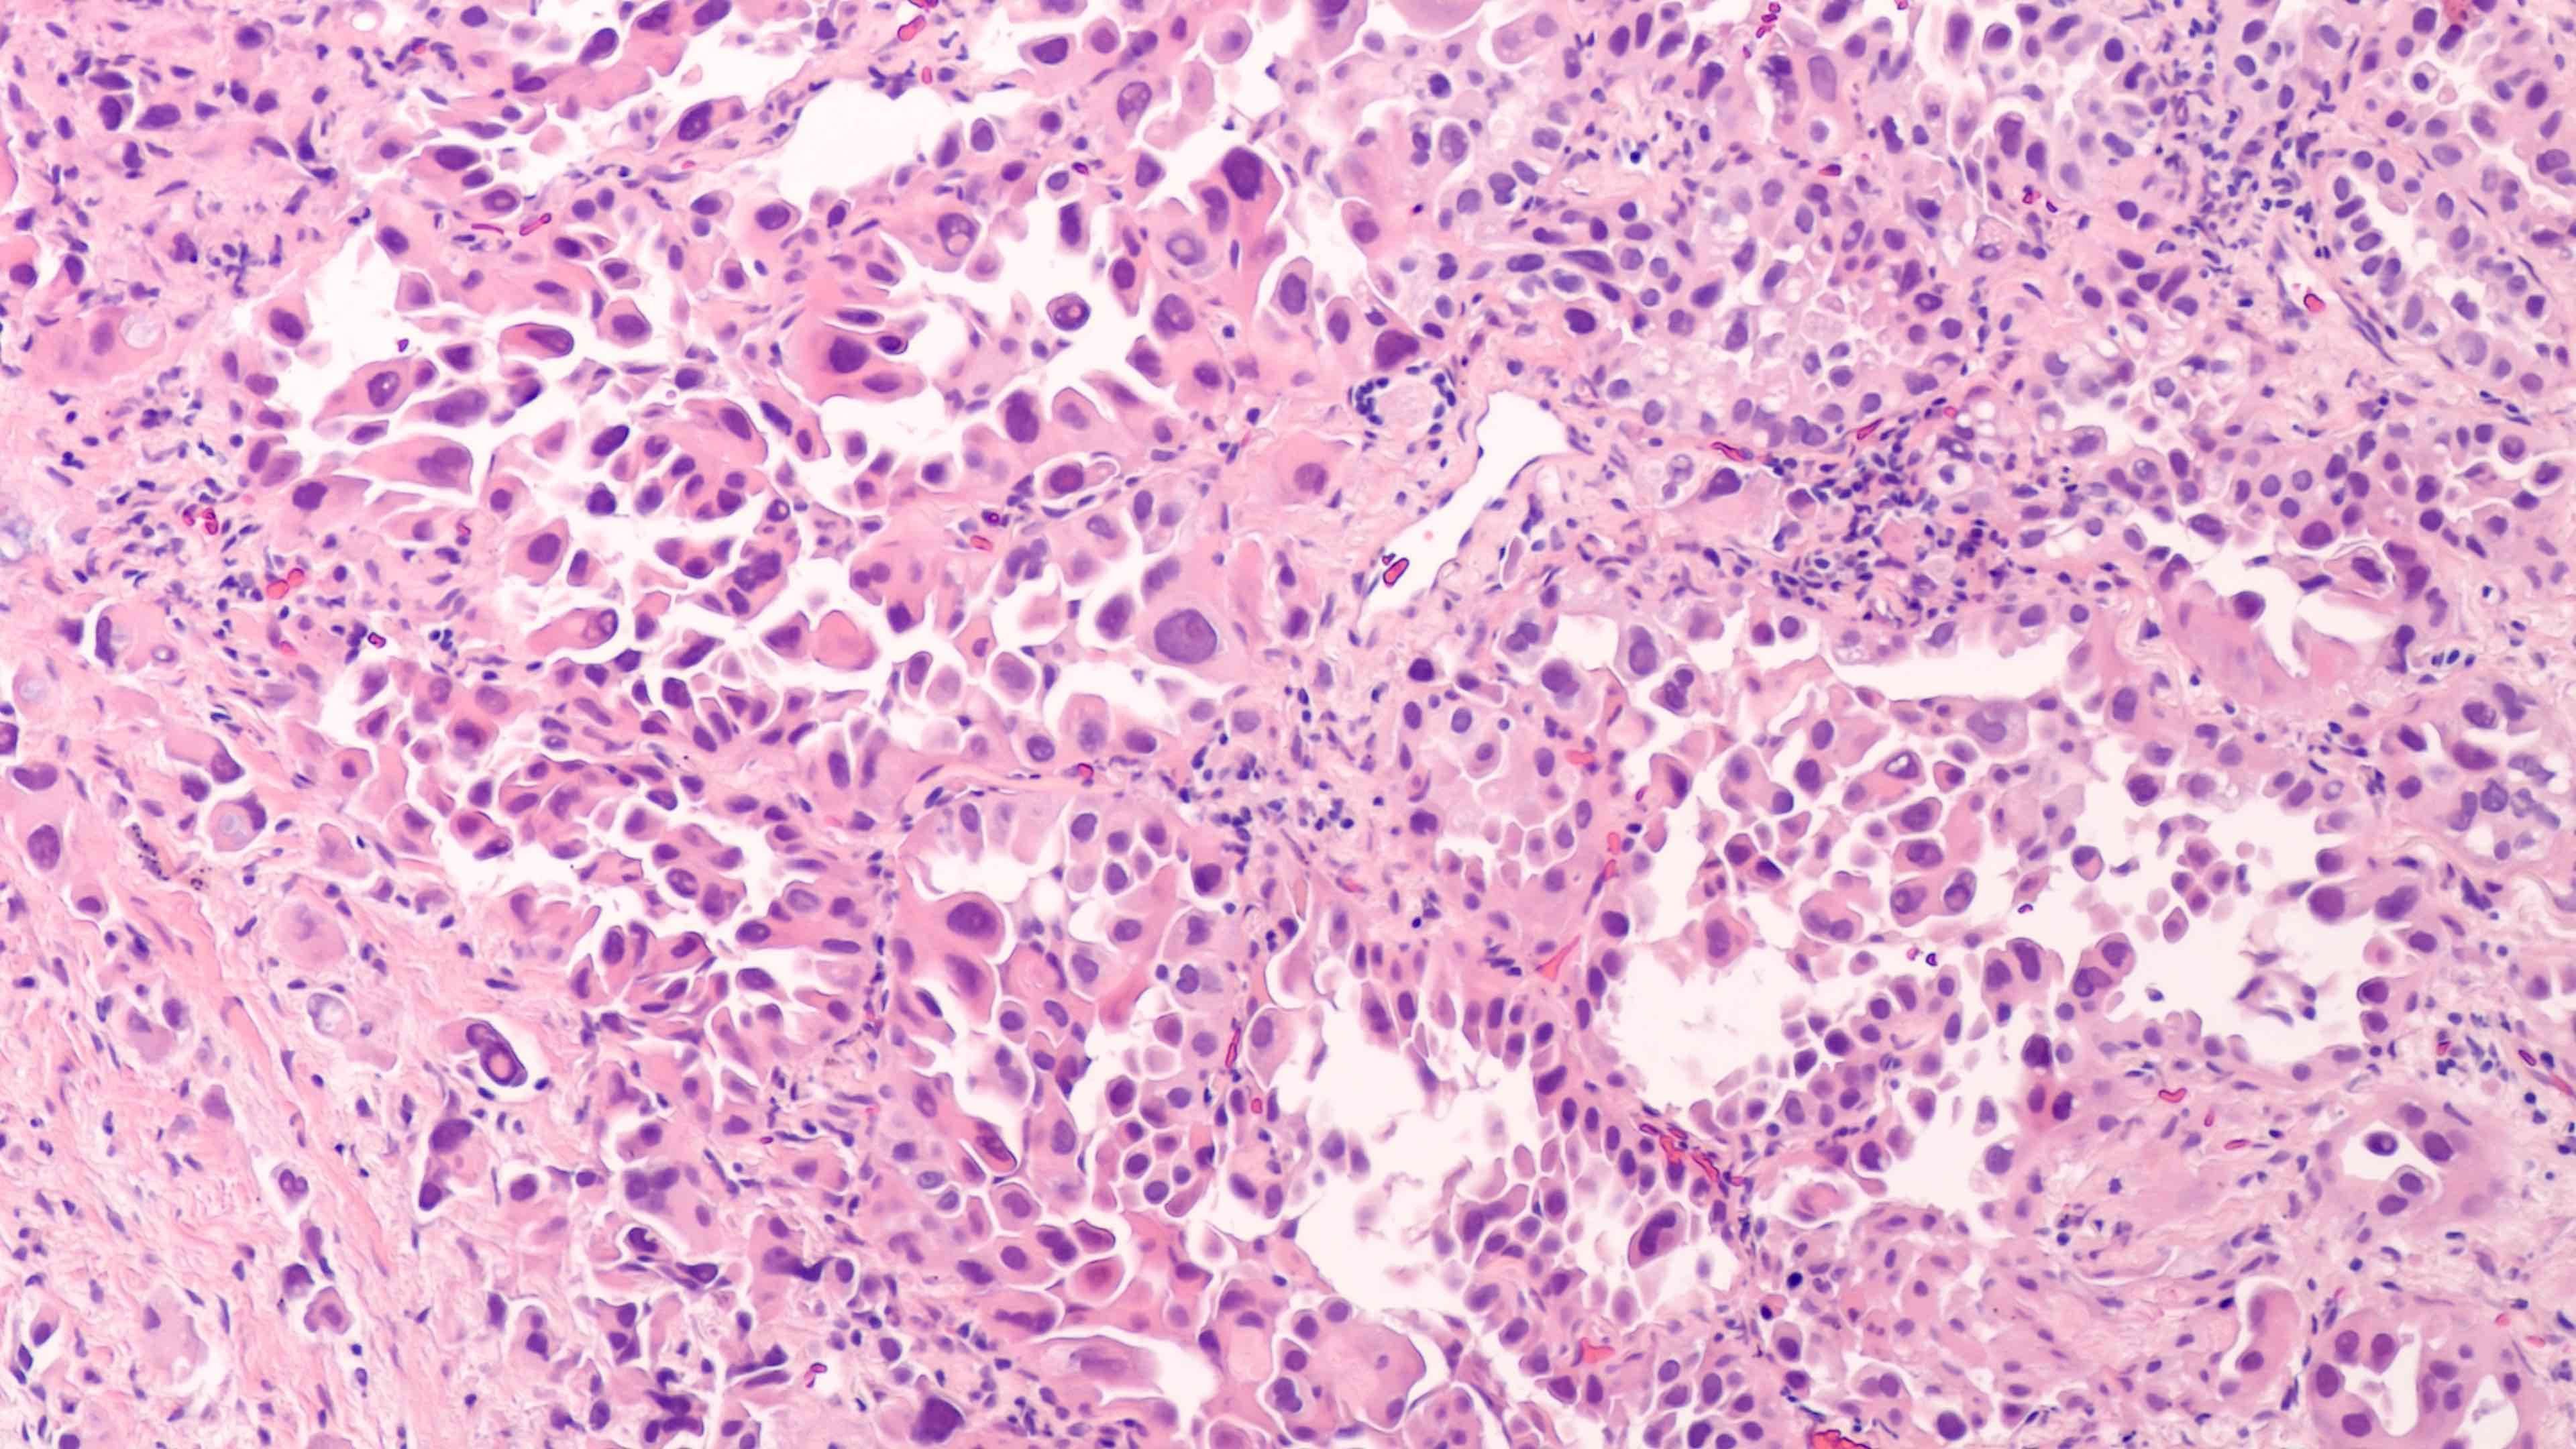

Lung cancer cells | Image credit: David A Litman - stock.adobe.com